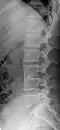

Several congenital block vertebrae in the transition from the thoracic to the lumbar spine and hemivertebrae. -